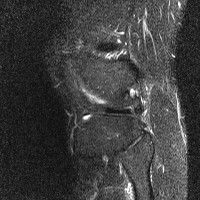

무릎 mri 간단히 봐주실 수 있으시나요 ㅠㅠ

안녕하세요 8년전 십자인대 수술하고 최근 무리한 운동에 무릎 불편감이 생겨서

mri 찍었습니다.

진단결과는 첫 찍은 병원에서 활액막염 이라는 진단을 받았습니다. 혹시 봐주실 수 있으실까요?

• 4번 째 사진

• 안녕하세요. 강성주 의사입니다.

올라온 MRI가 단편적이라서 정확한 진단에 어려움이 있지만 십자인대에는 큰 이상이 있지는 않은것 같으며, 무릎관절내 물이 있는 것으로 보아 활액막염의 진단이 맞을 것 같습니다.

하지만 단편적인 영상이기 때문에 촬영병원에서 정확한 판독지 등을 받으시는 것이 좋겠습니다.